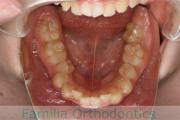

左下の奥歯が内側に倒れているのを治したいということで来院されました。かみ合わせが深い、上顎前突(出っ歯)の患者さんでした。上下左右から小臼歯を抜歯して、大臼歯を起こしながら治療を行いました。約3年、35回程度の通院をしていただきました。

かみ合わせが深いため、治療を行わないと前歯の裏側の歯茎を咬んでしまうリスクがありました。